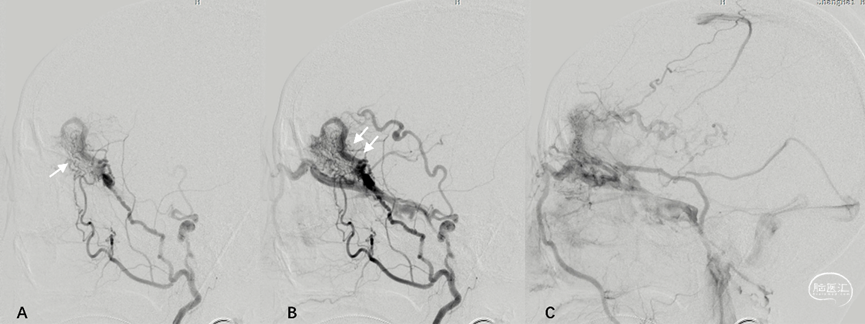

2.桥静脉型硬脑膜动静脉瘘(bridging vein type DAVF, BV-DAVF),即动-静脉移行起自硬膜固有静脉,经桥静脉硬膜内段向软膜静脉逆流。由于桥静脉向静脉窦直接引流受阻,动静脉瘘无法直接进入静脉窦,而通过侧枝吻合进入邻近静脉窦。影像学表现为桥静脉-软膜静脉早显,并早于静脉窦显影(图3)。

图3. 桥静脉型DAVF的血管构筑。侧窦区桥静脉型DAVF的起点位于桥静脉硬膜内段,由MMA(黑箭)供血,向软膜静脉逆流(A)。同侧乙状窦(双白箭)晚于桥静脉-软膜静脉间接显影(B)。脑静脉窦期显示静脉窦血流通畅,侧裂浅静脉回流被DAVF竞争性抑制(C)